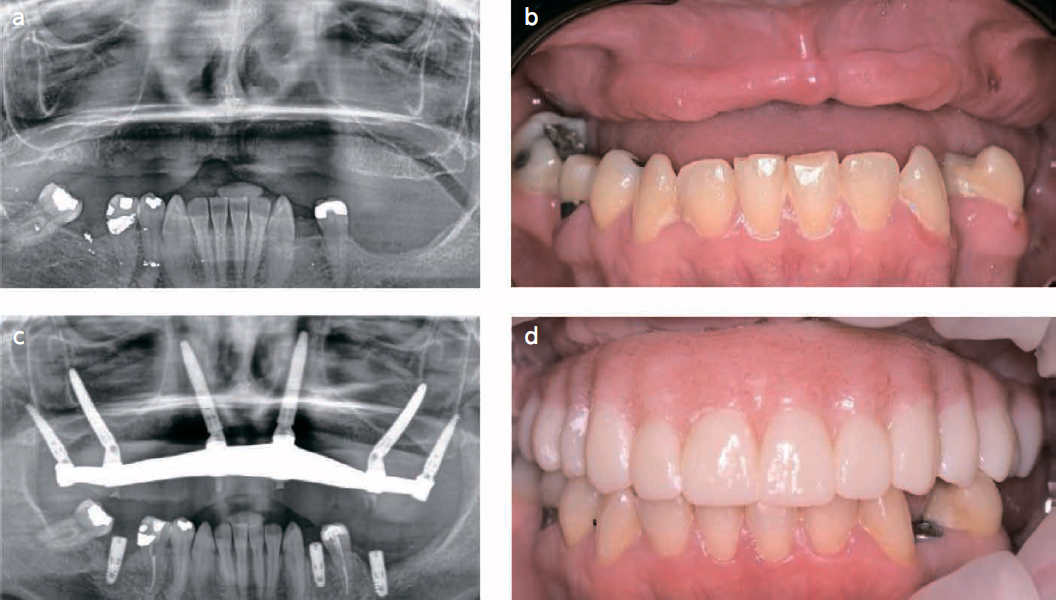

a) Female patient, 44 years old, with bone loss due to periodontal disease and a traumatic injury.

b) Clinical situation of the patient, before the surgery.

c) Following the PATZi algorithm in this case, first pterygoid implants were placed bilaterally P1, attention was then directed to the anterior region, where bilateral intra alveolar implants don’t achieve a primary stability, so extra alveolar implants that engaged the lateral nasal wall bone were achieved A2, traditional tilted implants and transsinus implants were attempt and don’t show primary stability Tx. PATZi protocol demonstrates the indication for zygomatic implants, so Z1 configuration zygomatic implants were placed satisfactorily. d) Clinical photography, after delivery of the final prothesis, rehabilitation with hybrid prothesis after 6 months.